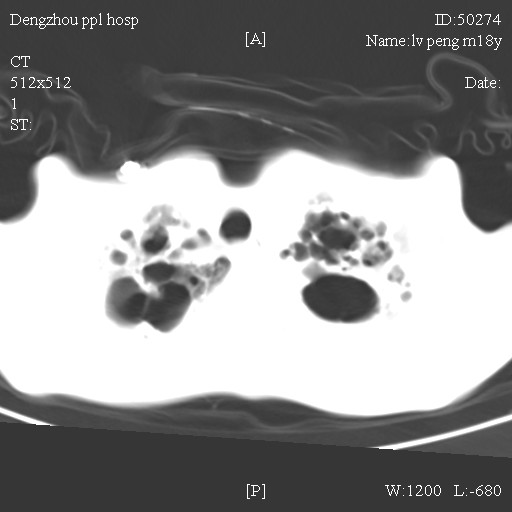

标题: CT10510:男.18岁,咳嗽咳痰两月.(有病理) [打印本页]

标题: CT10510:男.18岁,咳嗽咳痰两月.(有病理)

双肺布满大片状实变及网格状结节影,内参杂大小不等的气囊及空气支气管征,心脏增大。考虑:1 全身结缔组织疾病—系统性红斑狼仓?2 肺泡蛋白沉积症合并感染!

双肺布满大片状实变及网格状结节影,内参杂大小不等的气囊及空气支气管征,双侧胸膜腔少量积液,双下肺近膈面透亮度尚可,病人较年轻,病变较重(不知为什么上胃管?)考虑:1.胶原病肺部改变,2.组织细胞病x。结合实验室检查。

首先考虑组织细胞x病。两肺中上肺野多发囊腔,中下肺野内见多发小结节,并可见肺间质增厚。患者是男性,年龄较小。胶原性病变比较多见的类风湿、系统性红斑狼疮和硬皮病临床和影像均不是很支持,类风湿和系统性红斑狼疮的肺部表现最常见的是胸腔积液,硬皮病可见食管的扩张。

肺内多发斑片状、结节状、融合大片状及网格状影,多发薄壁空腔影,胸膜肥厚,纵隔、气管右移,考虑ⅲ型肺结核,多发空洞,继发肺间质纤维化。

双肺结核并播散.患者以肠梗阻入院,手术为肠结核.术后咳嗽做ct检查.